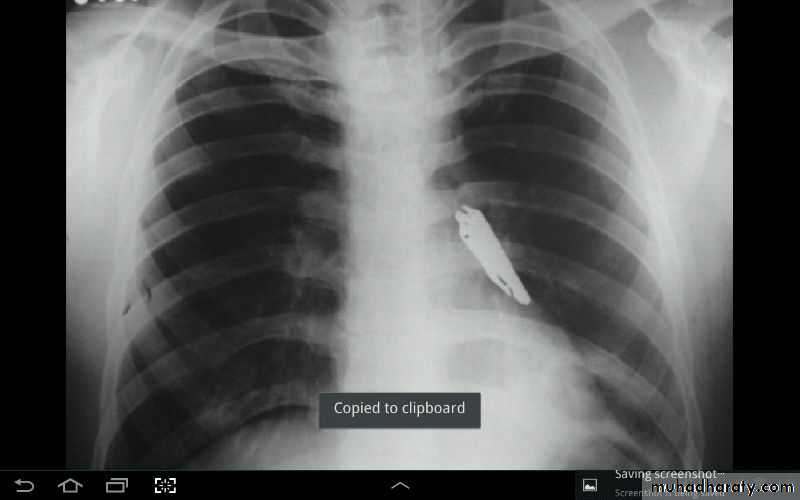

Foreign body in right bronchus

Foreign body in bronchus